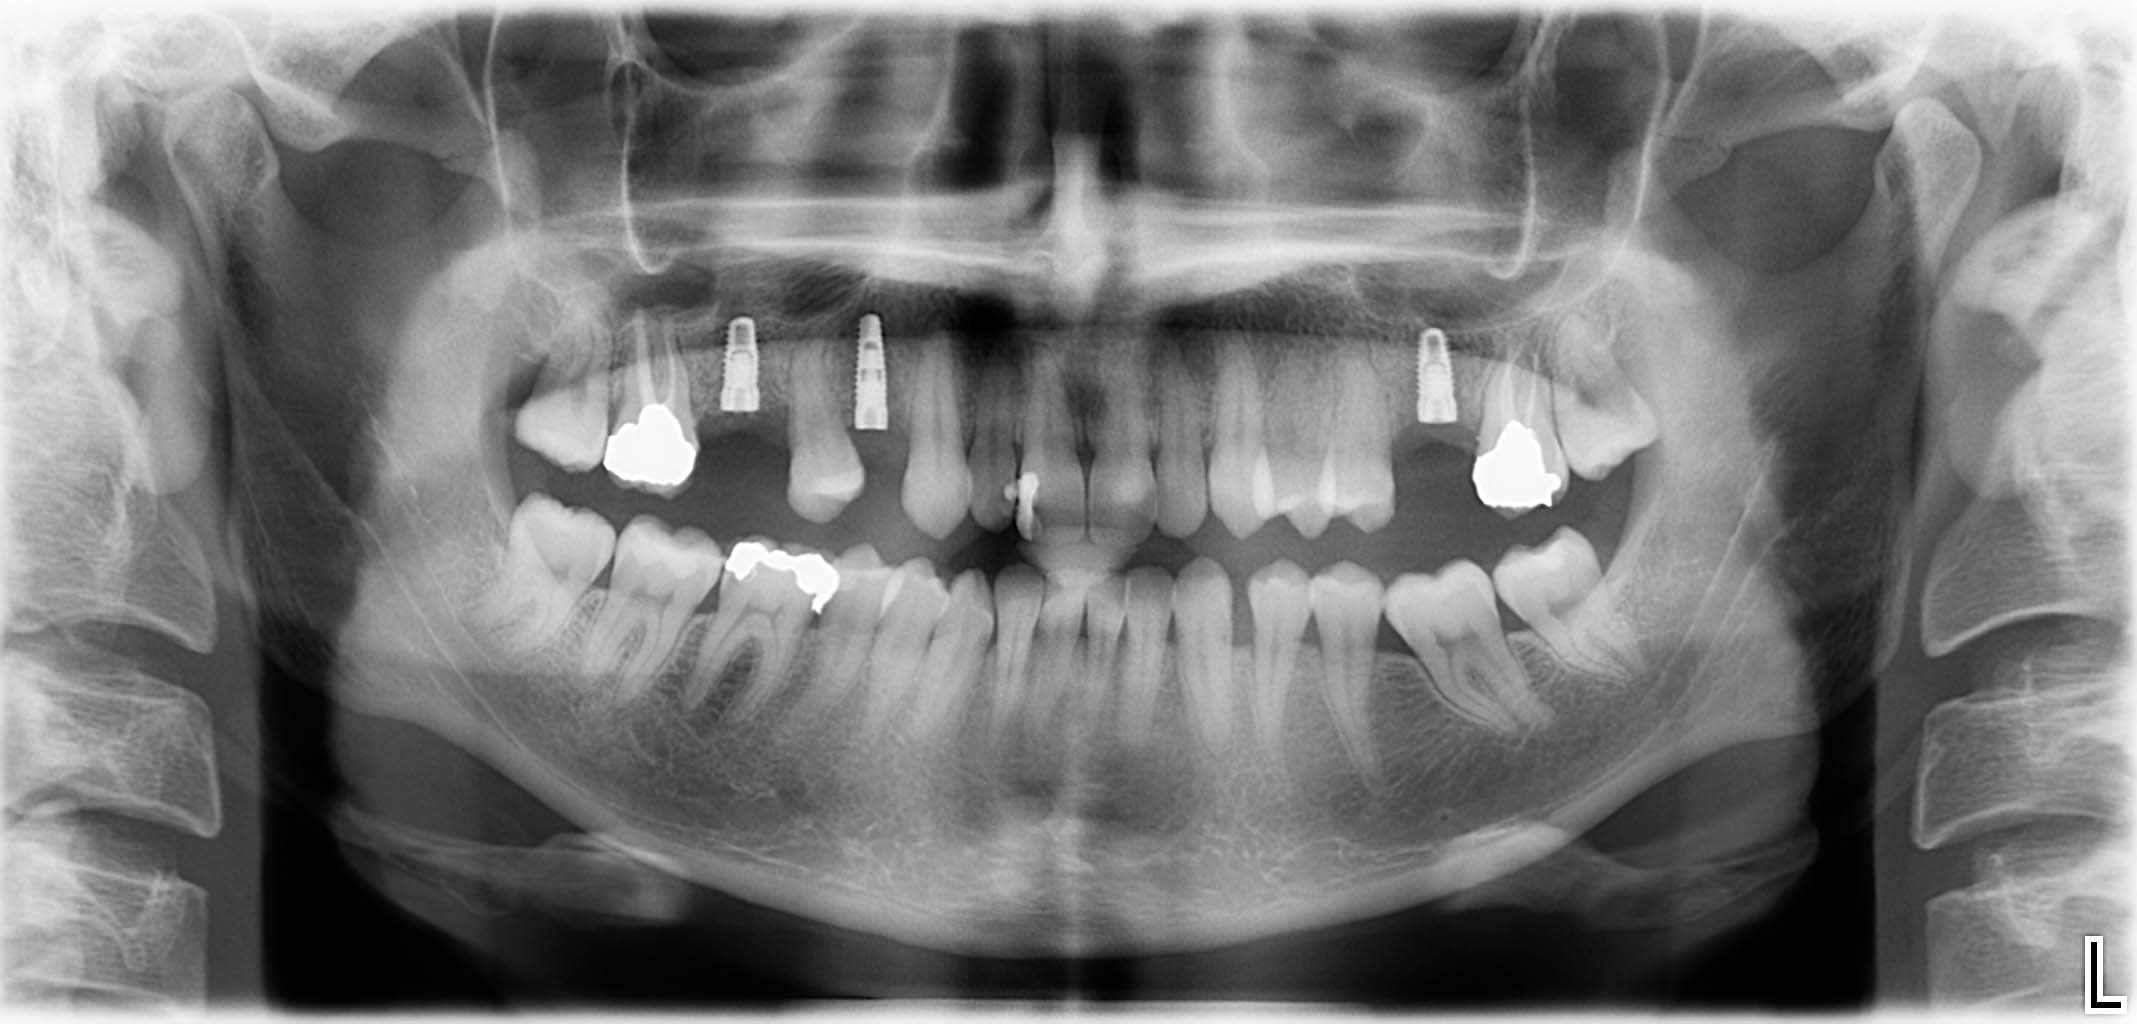

Erfolgreich implantierte Patientenfälle (klinische Fotos)